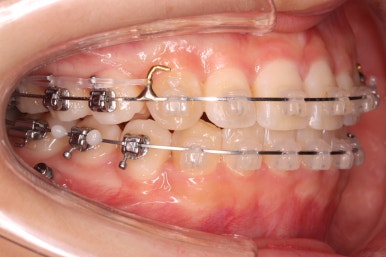

화살표에 보이는 부착물의 이름이 바이트터보 입니다.

깊게 맞물리는 앞니, 즉 과개교합을 개선하기 위해 일시적으로 이용하는 장치입니다.

굉장히 효율적으로 과개교합을 개선할 수 있습니다.

아랫니에도 이제 장치를 붙였습니다.

과개교합인 채로 아랫니에도 장치를 붙이게 되면 아랫니 장치가 깨물려서 다 떨어지거나 부서지기 쉽습니다. 따라서 바이트터보는 굉장한 역할을 하게 됩니다.

눈으로 보기에는 과개교합이 개선이 된 것처럼 보이지만 아직은 아닙니다. 바이트터보가 남아있는 채로도 어금니가 맞물려야 진짜로 개선된 것이죠.

위 사진에서 화살표 부분이 미니스크류인데요.

어금니쪽 잇몸에 아주 작은 나사가 보이실텐데요. 이것을 이용해서 전체 치열을 뒤로 당겨넣습니다. 물론 사랑니는 제거가 된 상태입니다.